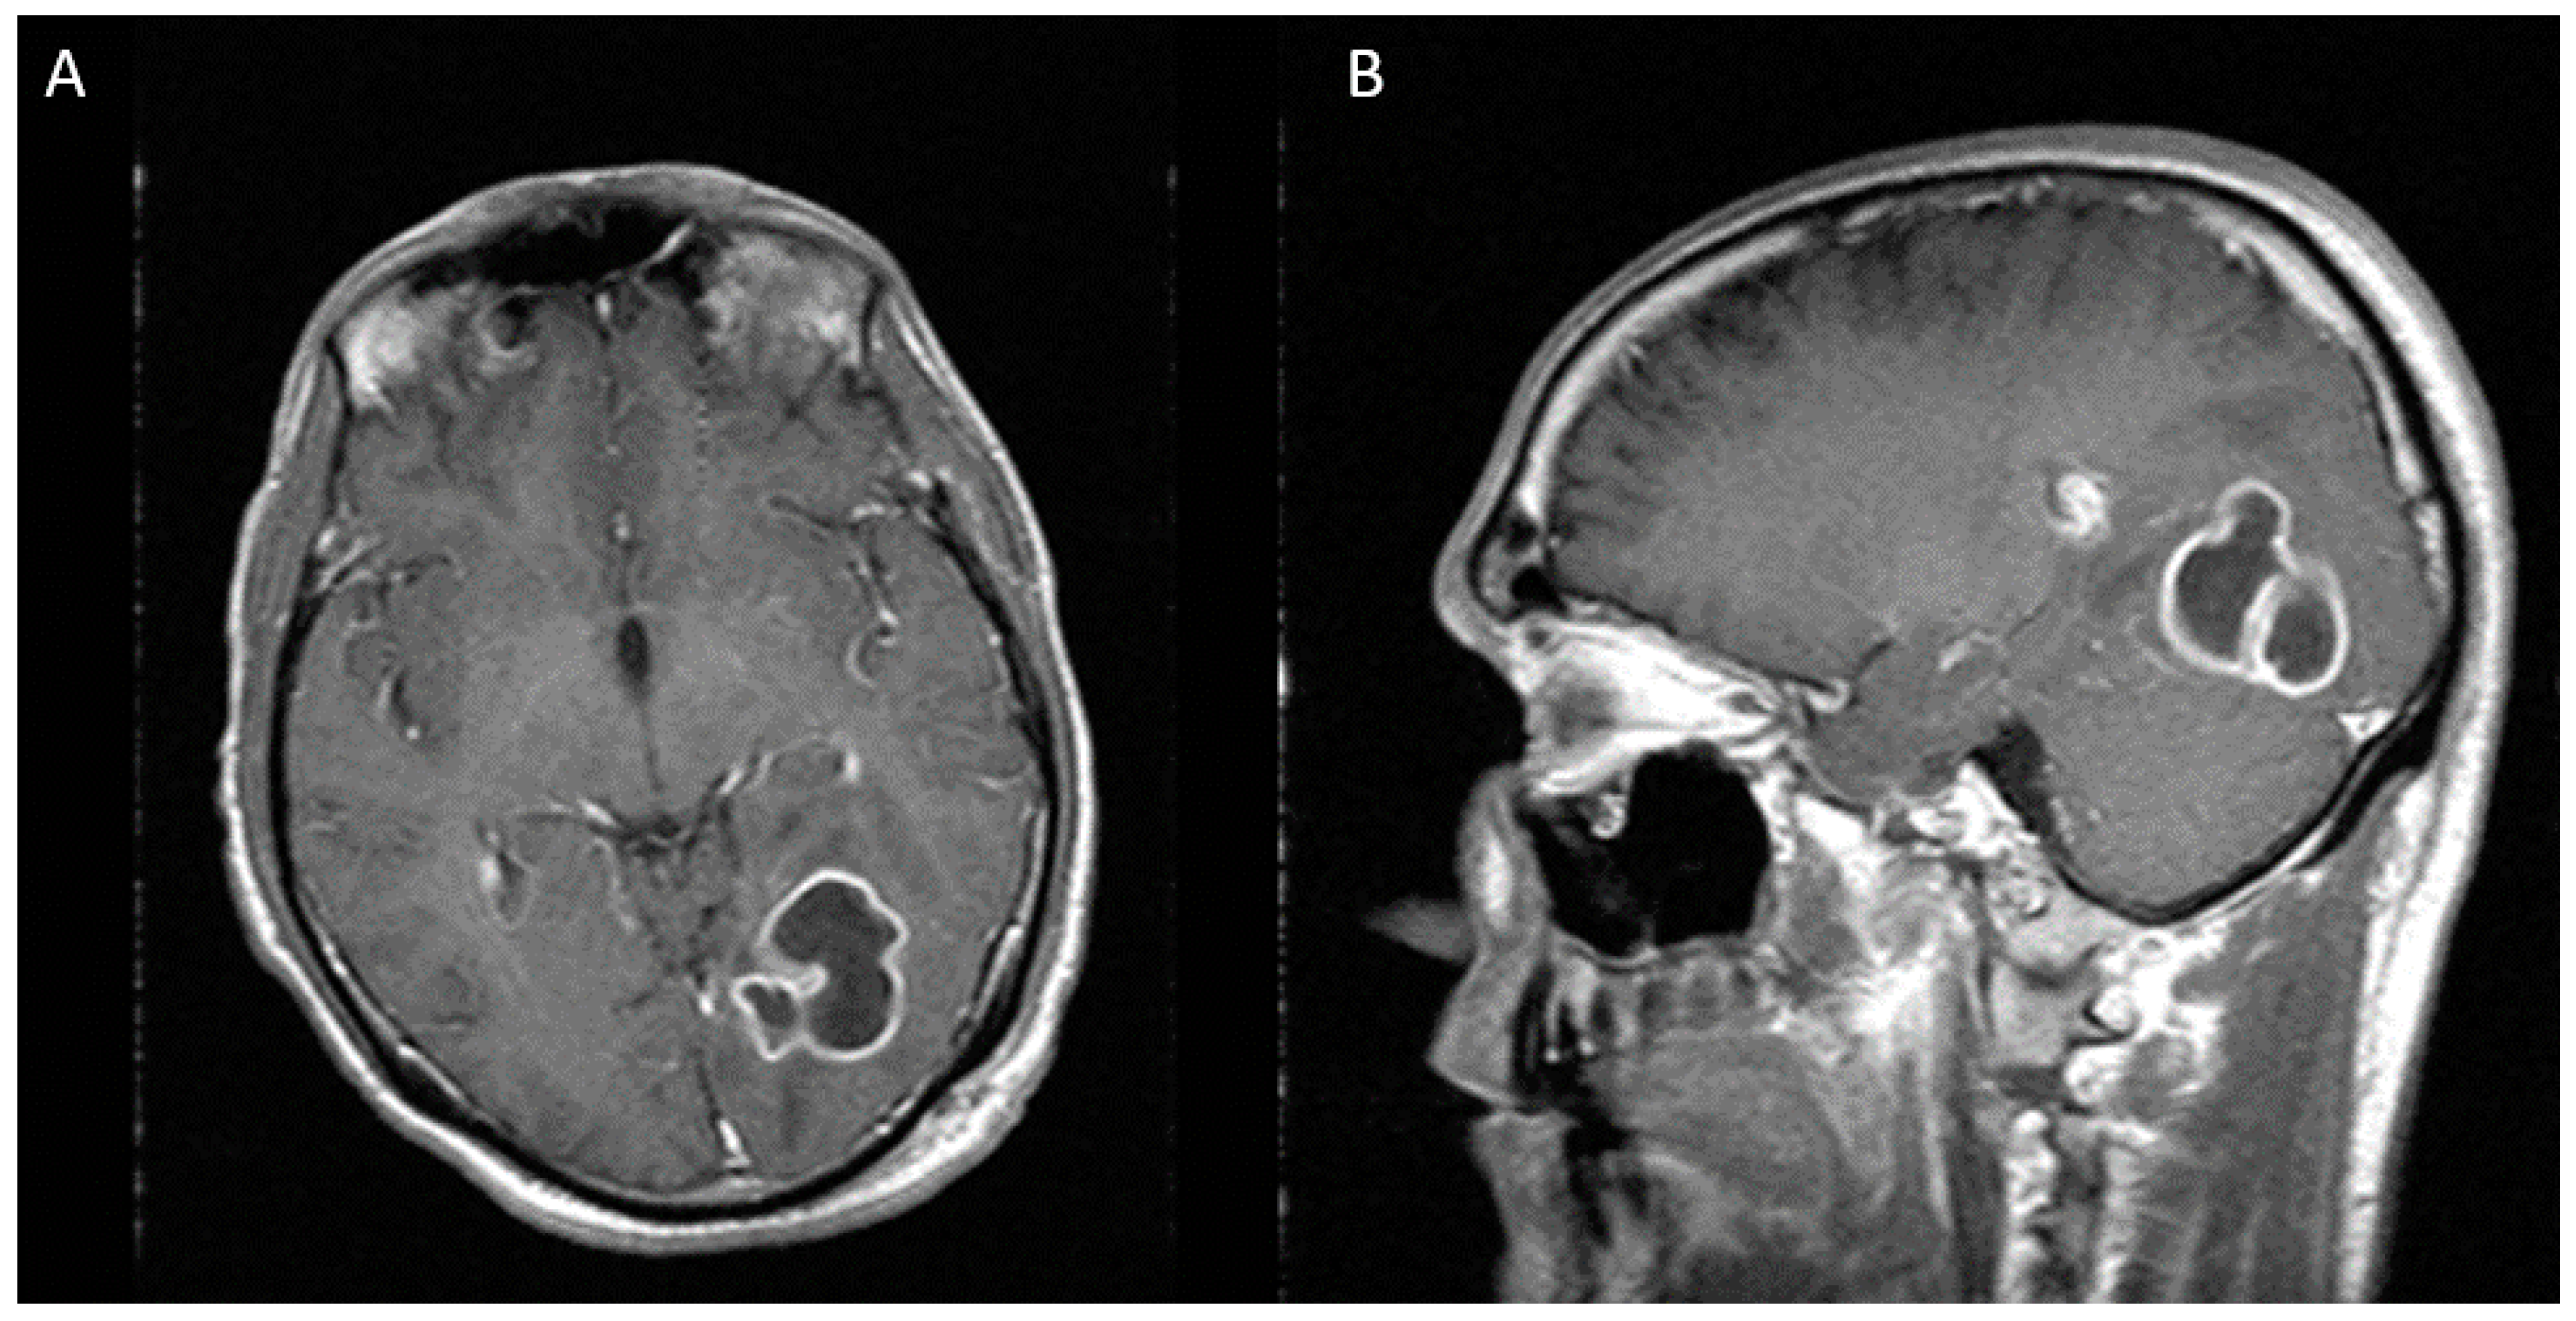

Figure 2.

Two weeks after first stereotactic needle aspiration, MRI demonstrates an increase in the abscess size, now measuring 36 × 33 × 40 mm. (A) Axial view (B) Sagittal view.